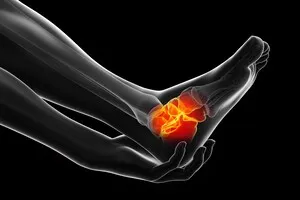

5. 관절염

관절 연골이 손상되어 발생하는 염증성 질환으로, 노화, 외상, 대사 질환 등 다양한 원인에 의해 발생합니다. 주로 통증, 부종, 관절의 뻣뻣함 등의 증상을 동반하며, 약물 치료, 물리치료, 그리고 심한 경우에는 관절 교체술과 같은 수술적 치료가 필요할 수 있습니다.